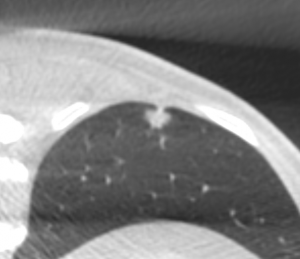

Sono stati inclusi 32 pazienti con 32 noduli polmonari inferiori ai 15 mm sottoposti ad agobiopsia percutanea mediante guida TC a fascio conico con braccio “a C” in un intervallo di 48 mesi da Gennaio 2018 a Dicembre 2021. Le procedure sono state eseguite con ago da biopsia automatico BARD MONOPTY © da 18 G. La biopsia è stata considerata diagnostica in presenza di esito istologico univoco, in assenza di necessità di ulteriori correlazioni anatomo-cliniche e/o in presenza di conferma istologica sul pezzo operatorio e/o con andamento clinico-radiologico al follow-up compatibile con l’istologia. Le complicanze principali della procedura comprendono emoftoe e PNX.

26 biopsie (81.3%) sono risultate diagnostiche. 17 (53.1%) sono risultate positive per malignità e 9 (28.1%) negative per malignità. Delle 6 biopsie non diagnostiche, 5 sono risultate lesioni maligne al follow-up e 1 paziente è stato perso al follow-up. Si sono verificati 18 PNX (56.3%) di cui 2 PNX (6.3%) con necessità di posizionamento di drenaggio toracico e 2 casi di emoftoe (6.3%) risolti con la variazione di decubito.

La TC a fascio conico é un valido supporto per l'agobiopsia percutanea di noduli polmonari di piccole dimensioni. I frustoli prelevati risultano diagnostici in un’ alta percentuale di casi con frequenza comparabile ai dati della letteratura riguardanti biopsie polmonari sotto guida TC spirale o TC a fascio conico. Il tasso di PNX è lievemente più alto che in letteratura, pur trattandosi per la maggiore di PNX di minima entità che richiedono esclusivamente il monitoraggio clinico.